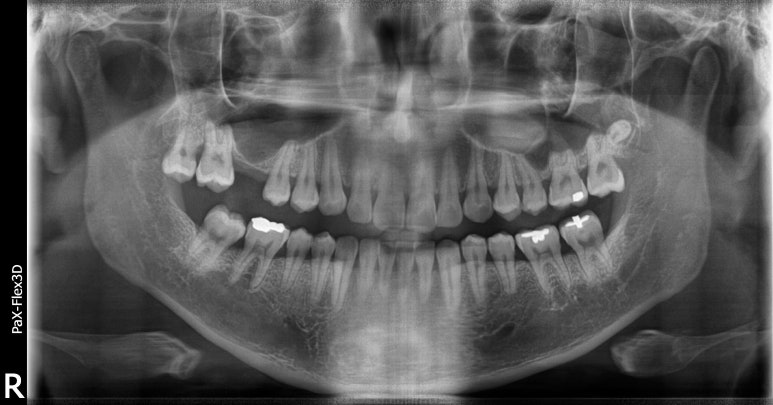

왼쪽 위(실제 오른쪽) 잇몸뼈가 부족하고 상악동막이 내려와있는 환자분 케이스

30대 남성

2022-10-22

위 사진을 보시면 왼쪽(실제로는 오른쪽) 치아가 결손되어 있는 부분에

무언가 까맣게 뼈 가까이 내려와 있는 모습을 보실 수 있습니다. 잇몸뼈도 얇고 부족한 것이 보이실겁니다.

만약 이 상태에서 임플란트를 식립한다면 어떻게 될까요?

뼈가 워낙 얇기 때문에 뼈와 임플란트가 잘 유착되기 어려울뿐더러 튼튼하게 지지하기도 어려울겁니다.

임플란트 인공치근이 상악동을 뚫고 들어가 구멍이 나거나 염증이 생길 수도 있고요.